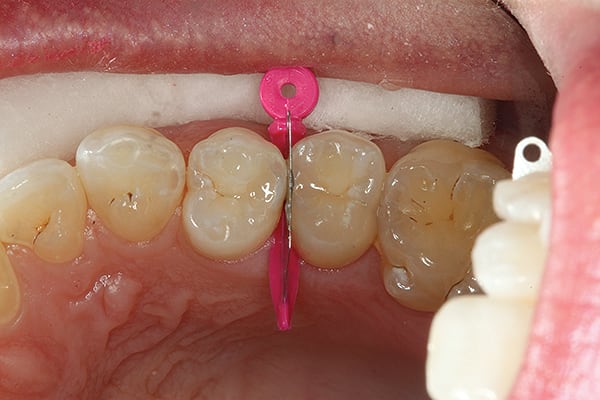

1. Initial incipient Class II decay. The first tunnel has been completed. Note the decalcification left on the proximal wall but the decay removed and the wall perforated through up to the matrix band (Triodent WedgeGuard, Ultradent, www.ultradent.com).